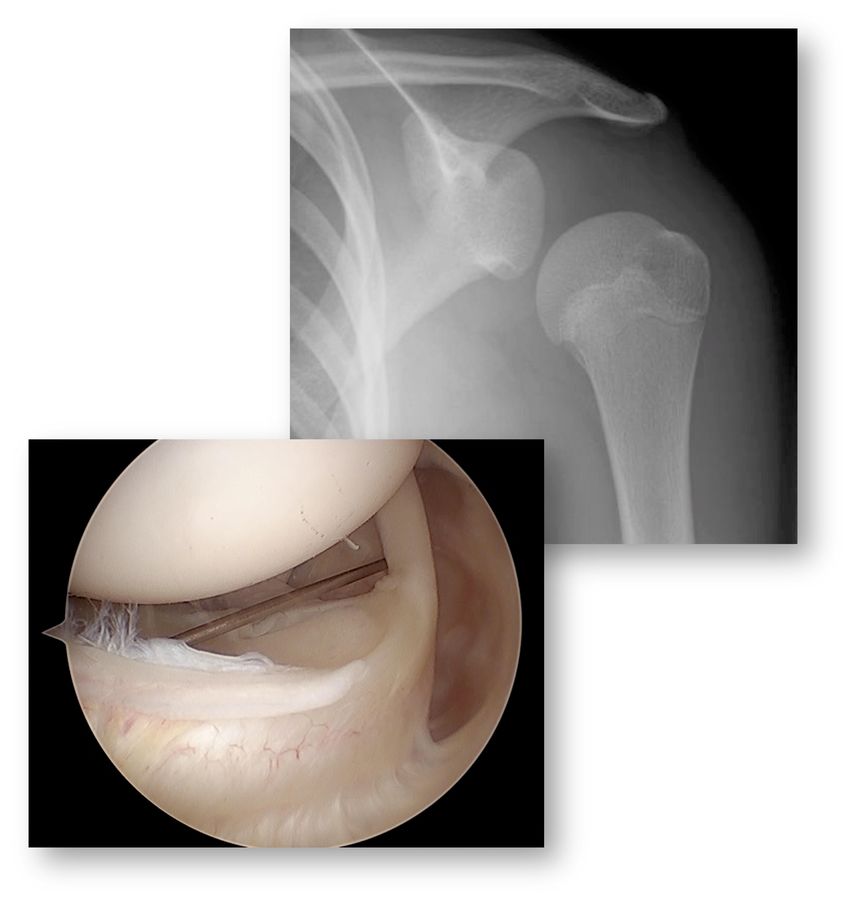

Chronische Kapseldysfunktion im Sinne von Kapselüberweite ist das pathologische Kriterium für die multidirektionale Instabilität (MDI). Obwohl es keine klaren und allgemein akzeptierten Kriterien gibt, kann ein überweites Intervall als auch ein Ausstülpen des Intervalls im Arthro-MRI als Zeichen dafür gesehen werden. Der Beighton’s Score kann zur Abgrenzung einer generalisierten Hyperlaxizität herangezogen werden. Bei mehreren oder atypischen Kombinationen von Beschwerden (Hautfragilität, hohe Kurzsichtigkeit, Hämatomneigung, multiple Allergien, kardiovaskuläre Probleme, entzündliche Probleme) kann eine rheumatologische Abklärung auf eine Kollagenopathie erfolgen (Abb. 5).

Abb. 5: Das Röntgen zeigt die enorme Schulterinstabilität, in der Arthroskopie zeigt der «Skybox View» die Kapselweite